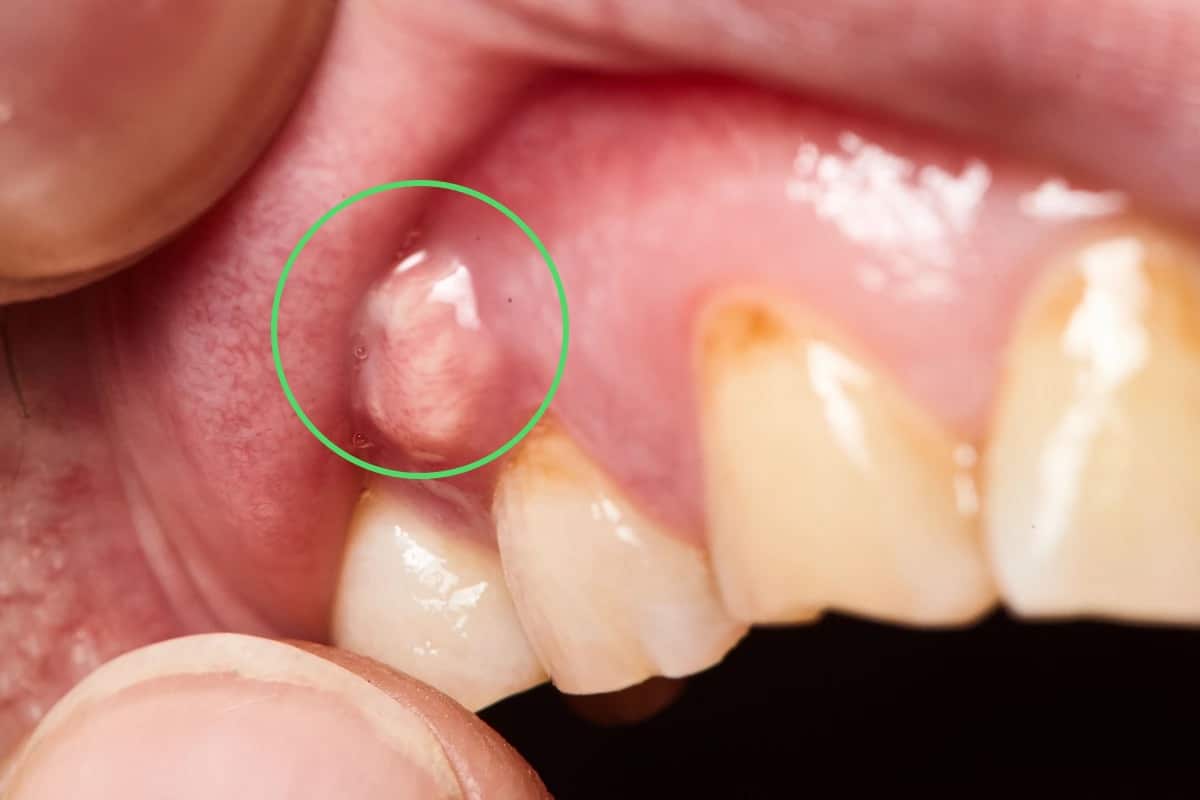

Viêm lợi phì đại là một tình trạng bệnh lý đặc trưng bởi sự tăng sinh quá mức của mô nướu. Từ đó dẫn đến hiện tượng nướu dày lên, sưng nề và có thể bao phủ một phần thân răng. Hiện tượng này thường là kết quả của phản ứng phì đại của mô lợi. Phản ứng này xảy ra đối với các tác nhân kích thích tại chỗ. Phổ biến nhất là mảng bám vi khuẩn còn mắc trong kẽ rằn. Đây là một yếu tố nguy cơ hàng đầu trong các bệnh lý nha chu.

Ngoài ra, tình trạng này cũng có thể phát sinh do tác dụng phụ của một số loại thuốc. Đặc biệt là các nhóm thuốc như thuốc chống động kinh (ví dụ: phenytoin). Ngoài ra là thuốc ức chế miễn dịch (cyclosporin), thuốc chẹn kênh canxi (như nifedipine). Tình trạng phì đại mô nướu không chỉ gây ảnh hưởng nghiêm trọng đến yếu tố thẩm mỹ. Điều này thể hiện qua việc nó làm cho răng trông ngắn hơn. Thậm chí khiến nướu chuyển sang màu đỏ đậm hoặc tím tái. Nó còn tác động tiêu cực đến chức năng sinh lý của khoang miệng.

- Nướu bị phì đại rõ rệt, phồng lên quá mức so với bình thường. Màu sắc nướu chuyển từ hồng nhạt sang đỏ tươi hoặc tím thẫm. Điều này phản ánh tình trạng viêm cấp tính hoặc mạn tính.

- Nướu dễ bị tổn thương và chảy máu khi đánh răng, dùng chỉ nha khoa. Hoặc trong quá trình ăn nhai, ngay cả khi tác động nhẹ.

Một số những bệnh nhân có tình trạng viêm lợi phì đại đã tiến triển nghiêm trọng. Lúc này mô nướu bị phì đại quá mức, bao phủ lên bề mặt răng. Đồng thời kèm theo dấu hiệu lây lan hoặc hình thành ổ mủ. Khi đó các biện pháp điều trị thông thường sẽ không còn hiệu quả. Lúc này, bác sĩ sẽ chỉ định can thiệp bằng các kỹ thuật ngoại khoa chuyên sâu.